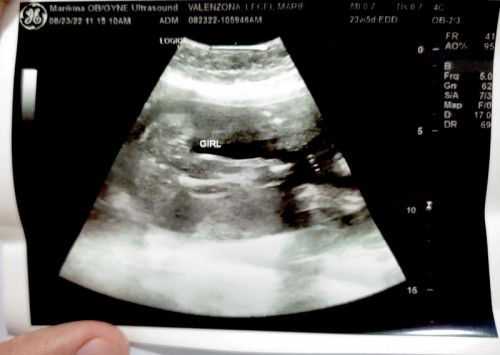

Hi po mga mommy,#1stimemom here. Sure na po ba yang girl? Di naman po sa may doubt ako kay OB, di lang po talaga ako marunong tumingin ng ultrasound, di ko po makita kung bakit sya girl hehe. 24 weeks po and naka cephalic na daw si baby. Gusto ko lang makasure para unti unti po makabili na ng gamit. Salamat po in advance sa makakapagshare ng thoughts. #1stimemom #advicepls #firstbaby #pregnancy

Hi po mga mommy, ##1stimemom here. Sure na po ba yang girl? Di naman po sa may doubt ako kay OB, di lang po talaga ako marunong tumingin ng ultrasound, di ko po makita kung bakit sya girl hehe. 24 weeks po and naka cephalic na daw si baby. Gusto ko lang makasure para unti unti po makabili na ng gamit. Salamat po in advance sa makakapagshare ng thoughts. #1stimemom #advicepls #firstbaby #pregnancy